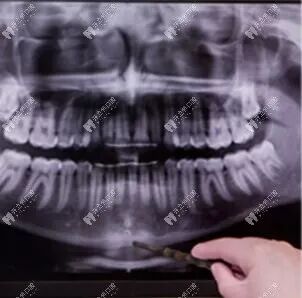

2、全景片(曲面断层片)

顾名思义,全景片就是拍摄全口牙齿。拍摄范围较广,在一张全景片上可以同时看到全口牙、双侧上下颌、颞颌关节、上颌窦下颌神经管、牙槽骨等部位情况。

可以了解牙根下是否有囊肿,周围骨头是否吸收,牙槽骨内是否有埋伏牙、多生牙等。